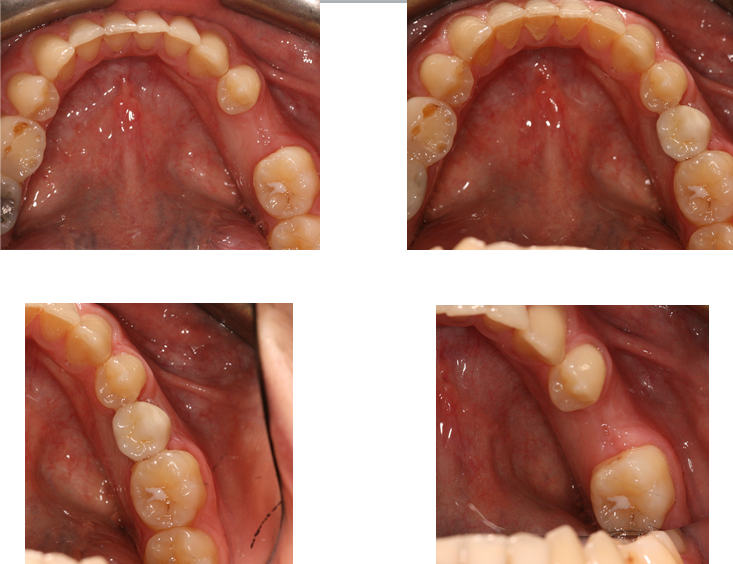

Here at Aesthetic Dental Zone we embrace new concepts, guided implant surgery provides a solution where doctors can plan an implant virtually, and then accurately place an implant in the safest, predictable and efficient manner.

With guided surgery, we place the implant for the best aesthetic result and can predict accurately how much room will be needed for the crown and for any veneered superstructure that may go over the abutment.

From a single missing tooth to an edentulous jaw. It aids your Doctor to diagnose, plan the treatment and place your implants based on restorative needs and surgical requirements.

Following an initial Implant Consultation and CBCT scan (3D Scan of your jaw) we can get to work on your specific Implant case.Guided Implant Surgery takes away the need to be too invasive when placing your dental implants.

It is extremely accurate, more comfortable and the healing time is reduced.Guided Implant Surgery is a state of the art technology, trust in us to make your implant process as simple and easy as possible.